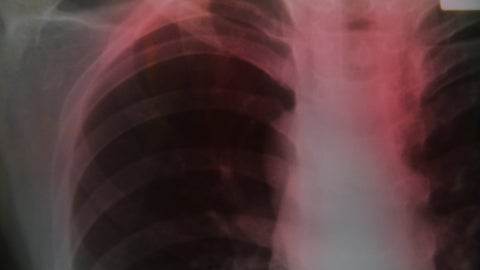

Vitaly Gariev on Unsplash" />According to the World Health Organization (WHO), a total of 1.23 million people died from tuberculosis (TB) in 2024 (including 150 000 among people with HIV). Globally, TB is the world’s leading cause of death from a single infectious agent and among the top 10 causes of death.